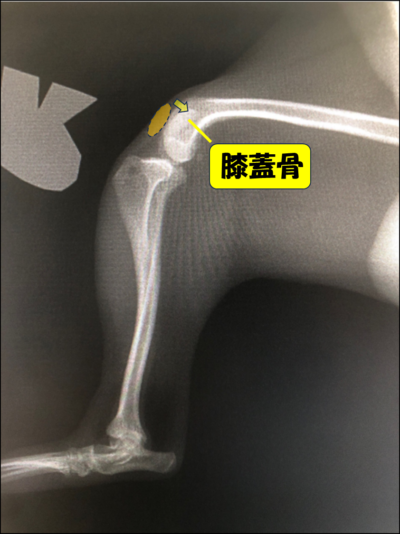

膝蓋骨脱臼(通称パテラ)とは、本来は膝蓋骨(膝のお皿の骨)が大腿骨(太ももの骨)の真正面になければいけないのに、膝蓋骨が脱臼してしまう病気です。

診断

・触診

・レントゲン検査